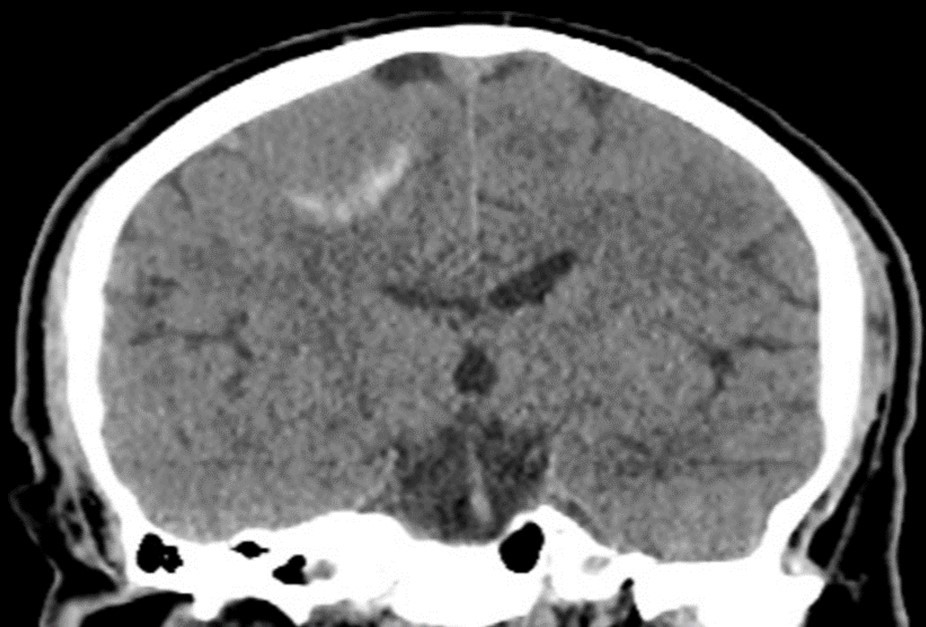

Treatment planning for LINAC-based radiosurgery has been performed by ERGO ++ (CMS, Elekta, UK) radiosurgery planning system. Optimal target coverage and normal tissue sparing has been achieved by using a single 360-degree arc, double 360-degree arcs, or five 180-degree arcs in radiosurgery planning. Synergy (Elekta, UK) LINAC available at our department has been used in delivery of treatment. Delineation of the target volume on planning CT and MR images has been optimized by selecting the appropriate windows and levels for radiosurgery planning. Sagittal and coronal images have been used in addition to the axial planning CT images to achieve accurate contouring of target volume and critical structures. Arc Modulation Optimization Algorithm (AMOA) has been utilized for optimization of target volume coverage and critical organ sparing. Figure 1 shows coronal CT image of a patient with atypical meningioma, and Figure 2 shows the corresponding coronal MR image of the same patient with atypical meningioma.

Figure 2.Corresponding coronal MR image of the same patient with atypical meningioma

Corresponding coronal MR image of the same patient with atypical meningioma